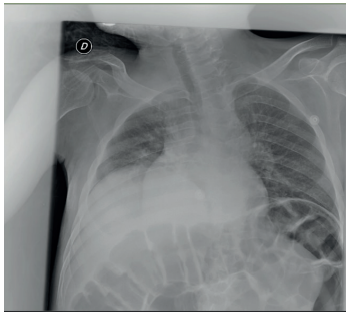

Es frecuente que en las distintas fases de la enfermedad se desarrollen infecciones, en forma de otitis media serosa. Las infecciones respiratorias altas debidas a alteraciones estructurales que se daban en otros subtipos de MPS no son tan frecuentes en el Síndrome de Sanfilippo. Con la evolución de la enfermedad son frecuentes las neumonías aspirativas que son causa de morbimortalidad21.

Como en otros tipos de MPS, para el uso de anestesia general y sedación hay que tomar una serie de precauciones. A pesar de que estos pacientes con MPS III raramente presentan alteraciones a nivel de la columna cervical, se ha podido demostrar que existe mayor riesgo de complicaciones con la intubación orotraqueal que con la máscara laríngea, siendo ésta aconsejable32.